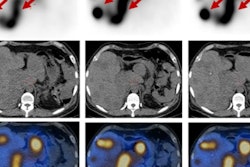

Maximum intensity projection shows relative positions of organs and tumors in the simulations with sample activity levels and plot of counts for 2D detector array (b). Red boxes represent detector positions that the algorithm selected for optimal dose estimation. The vest covers approximately 18 cm of the torso. Images courtesy of Miyaoka et al and SNMMI.Thus far, the researchers have performed simulation tests on vests with 15 sensors using acquisition times of two minutes. The trial found that activity in each object within the phantom appropriately decayed, and based on these results, the researchers determined the optimum time for monitoring with the vest.